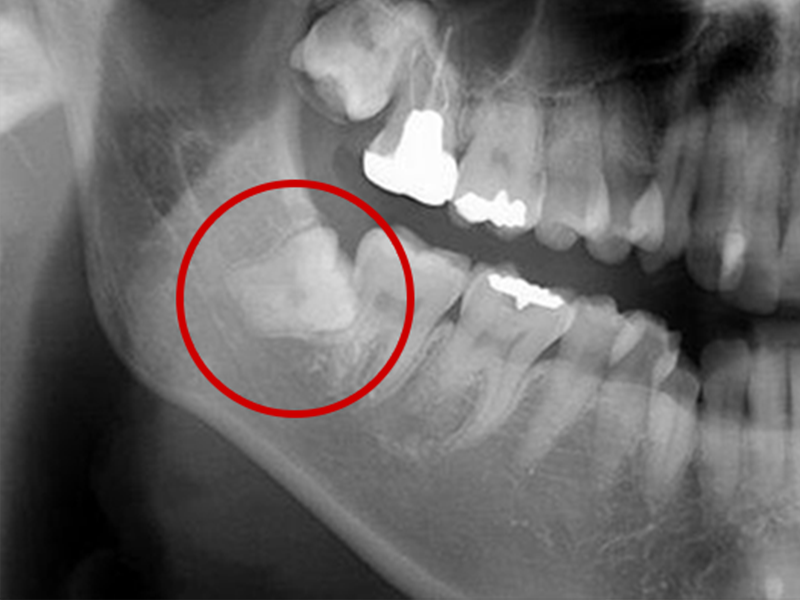

親知らずの抜歯について

親知らずとは大臼歯(大人の奥歯)の中で一番後ろに位置する第3大臼歯です。

智歯とも呼ばれ20歳前後で生えてくることが多く、一般的には上あごの左右2本と下あごの左右2本計4本ありますが、もともと親知らずのない人や4本揃っていない人など、個人差があります。

親知らずによる痛みの原因

親知らずは横や斜めに生えてきたり、歯ぐきがかぶっていることがあります。そのため親知らずの周囲には細菌が残りやすく、トラブルを起こし、痛みの原因になります。

親知らずが周囲に以下のような悪影響をもたらしている場合は、早めの抜歯をおすすめします。

- 親知らずの隣の歯がむし歯になる

- 親知らずの周りの歯ぐきが腫れる(智歯周囲炎)

- 生えてきた親知らずが、頬や歯ぐきの粘膜を傷付け口内炎となる

- 親知らずがかみ合わせに影響を与え、顎関節症になる

- 歯が押されて歯ならびが変わってしまう